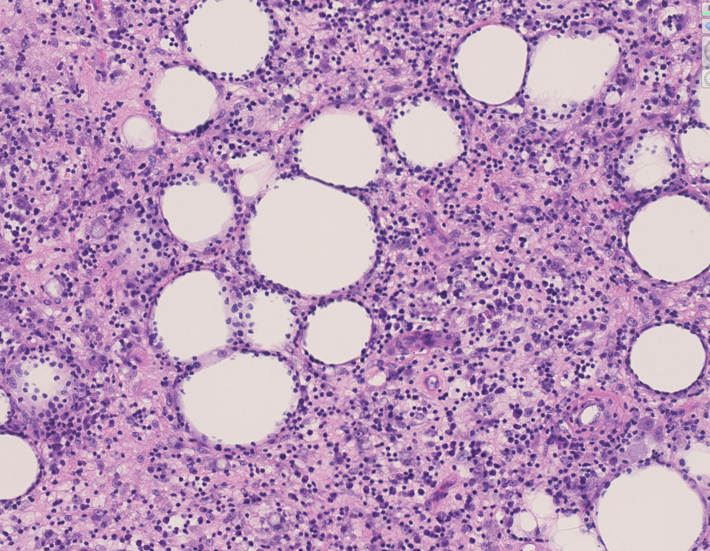

皮膚生検組織 サムネイルをクリックすると大きな画像がみられます。

組織所見*16*17*18

皮下組織に優位な, 小~中型 Tリンパ球の密な浸潤が特徴。ときに大型リンパ球や組織球が混在する。 リンパ球の異型は, わずかなものから明瞭な異型を示す症例までさまざまである。